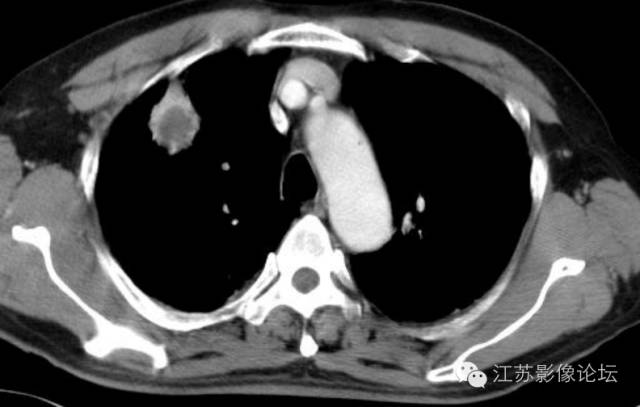

肺部结节的CT鉴别特征

脓腔见于炎性病灶

最常见于错构瘤和结核球;错构瘤30%有爆米花样钙化,结核球常见弧形或环形钙化;而砂粒状钙化常见于恶性结节,但很少见。